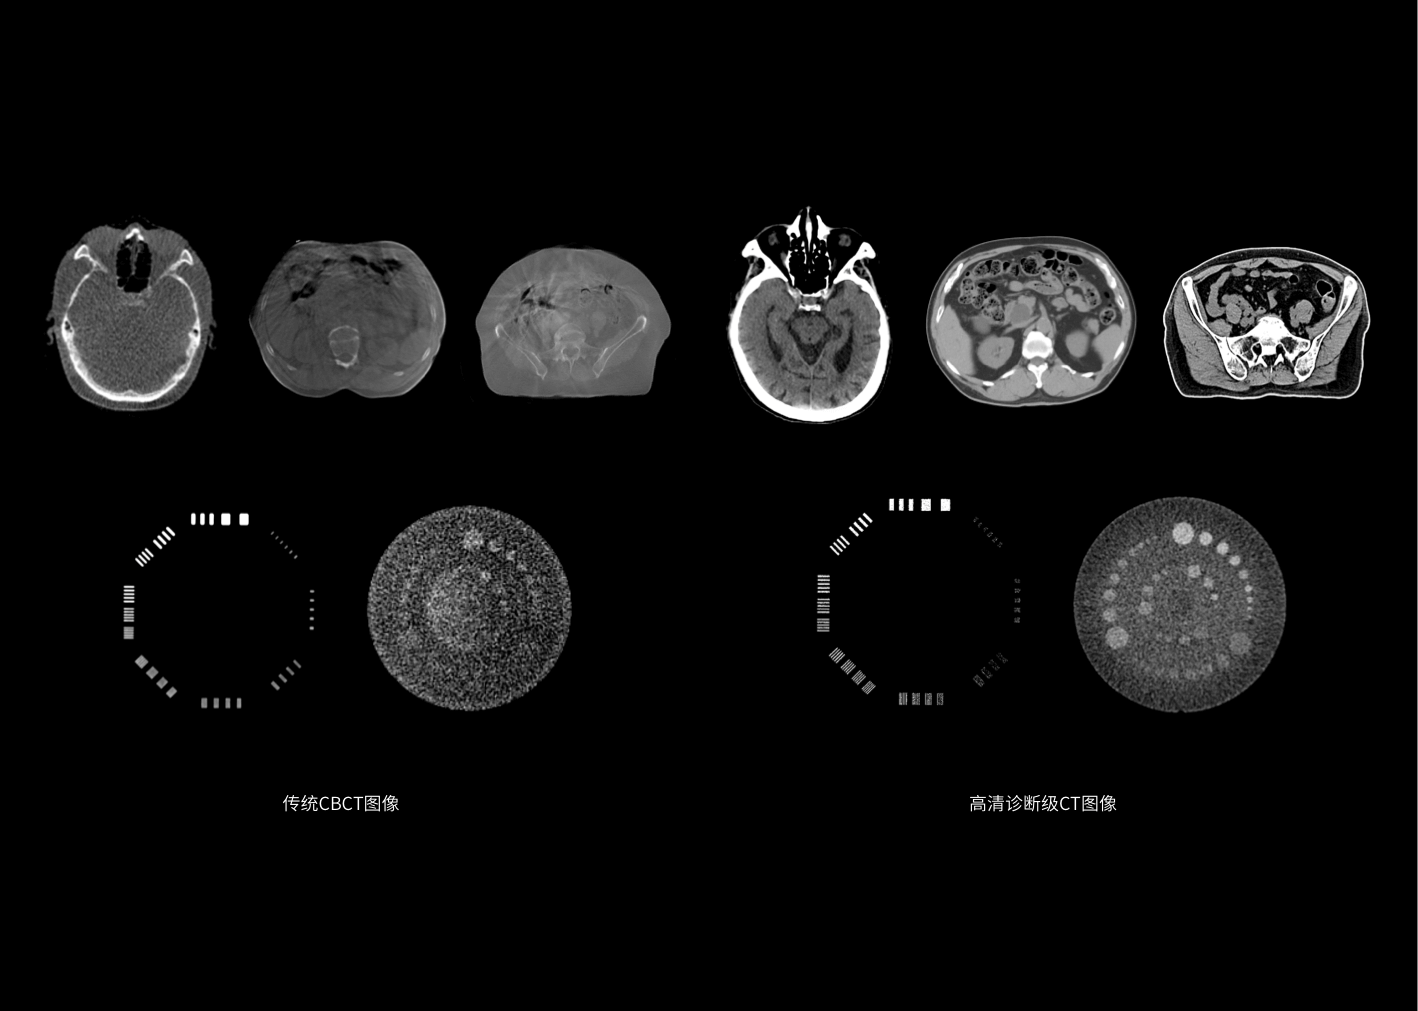

开创诊断级螺旋CT与直线加速器一体化跨界融合,依托高清诊断级图像引导,革新智能临床工作流程,达到精准放疗新高度,拓展放疗新应用,开启个体化精准放疗2.0时代。

50cm FOV, 100cm扫描长度,满足多种场景下的CT影像大成像范围要求。

诊断级CT精确的电子密度信息提供精准剂量计算的金标准。

诊断级高清CT助力监测肿瘤变化,及时调整治疗方案,护航各分次放疗精确实施。